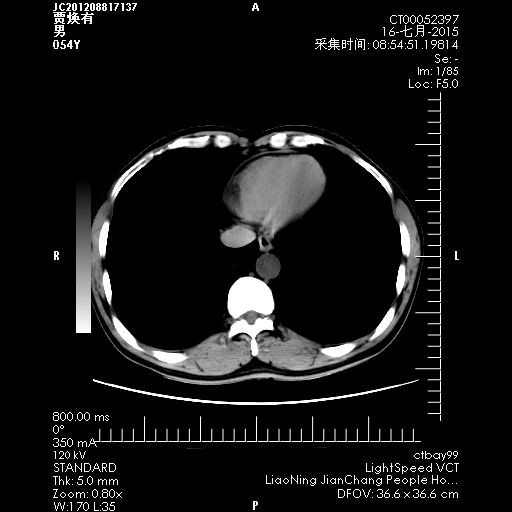

CT50850:男,54岁,腹腔多发占位性病变为主述。

本帖最后由 cefcmj 于 2015-7-17 22:07 编辑 男,54岁,腹腔多发占位性病变为主述,腹部CT平扫+增强检查,希望各位老师给予指导。

腹盆腔可见多发大小不一软组织密度及囊样占位,部分呈 斑片状及环状强化,肿块内低密度未见强化,考虑多发性神经钎维瘤?恶性间质瘤?